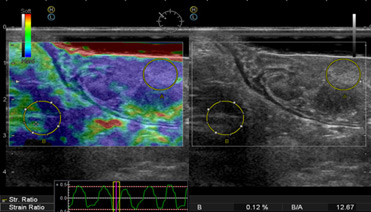

Ультразвуковое исследование прямой кишки. Ультразвуковая компрессионная эластография ворсинчатой опухоли прямой кишки.